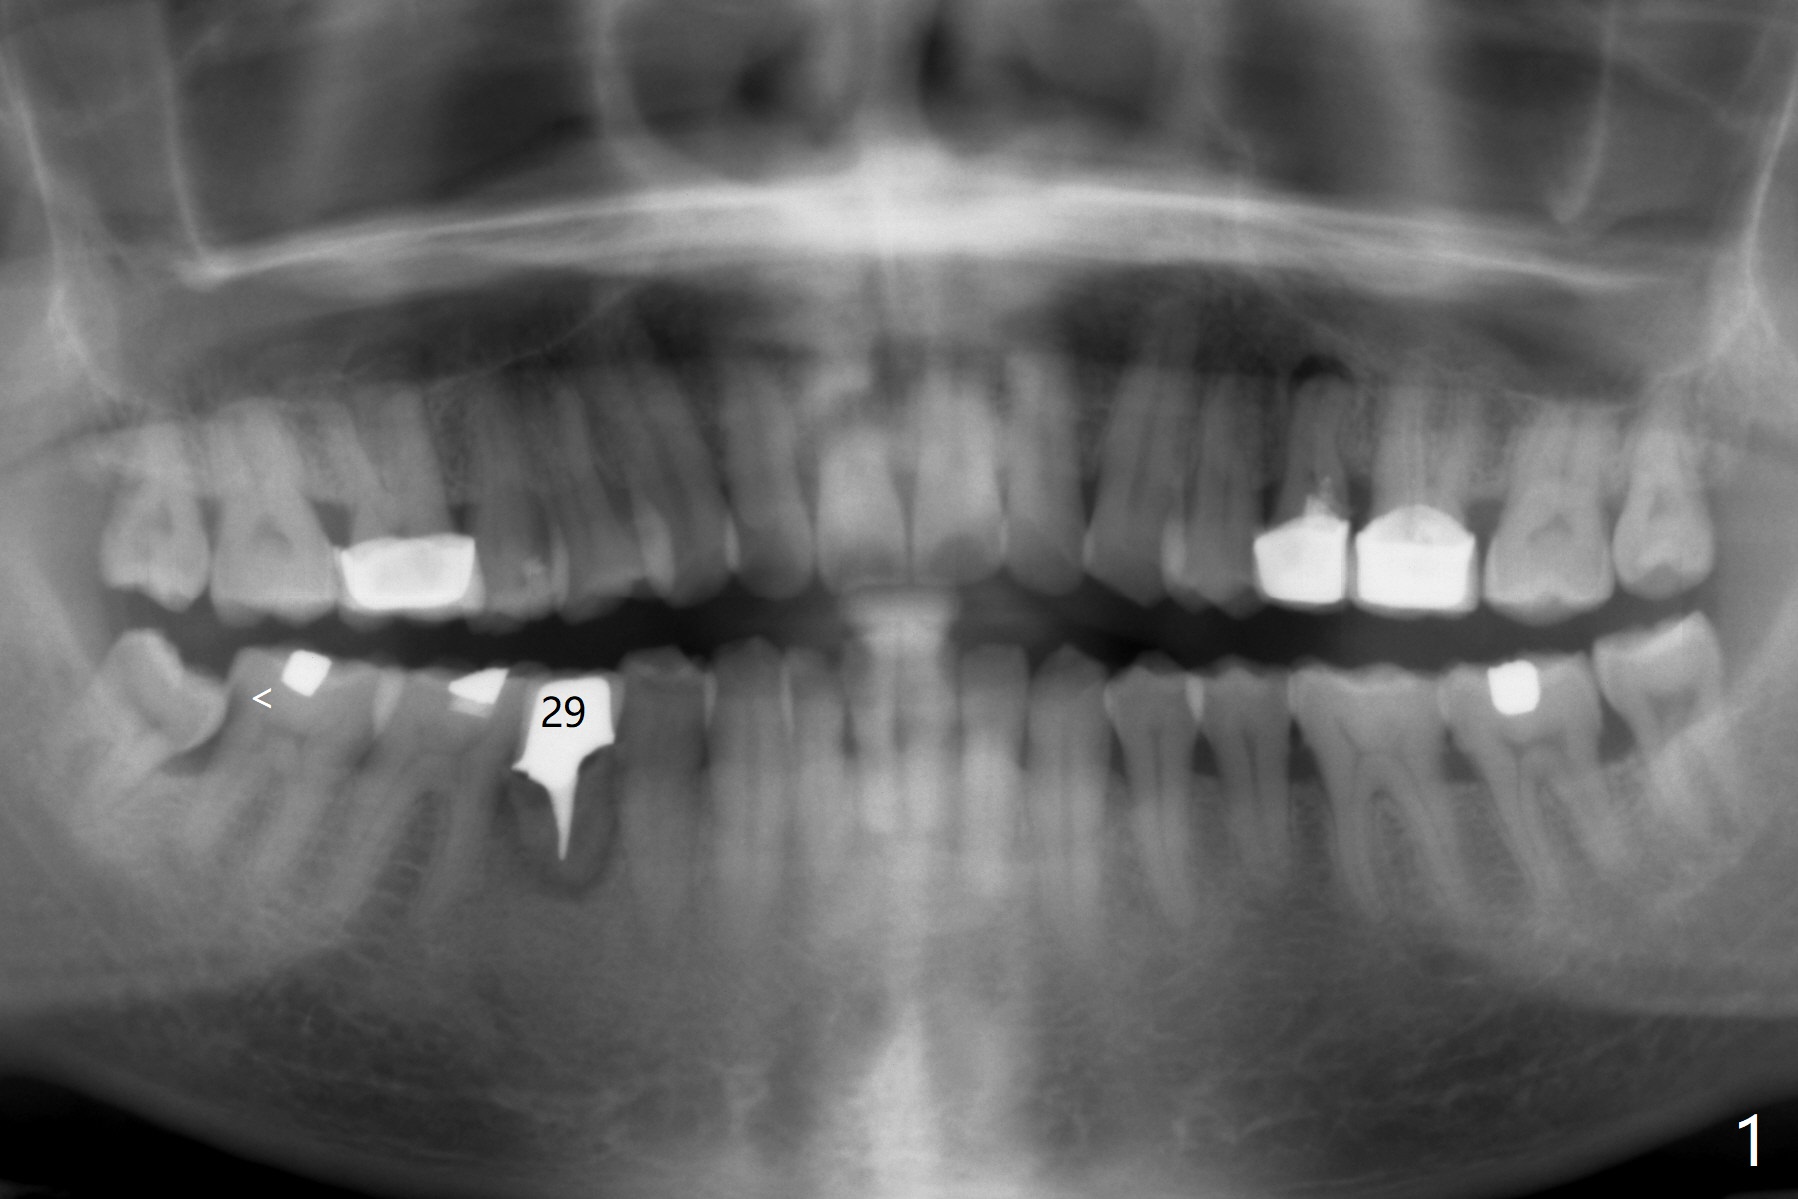

When a 46-year-old man presents with new patient examination, the tooth #29 has root fracture with a crown in place (Fig.1). A year later when he returns for #32 extraction, the crown is lost with displacement of the distobuccal (Fig.2,3 DB) portion of the root. The gingival recession is severe. When the root is removed, an implant will be placed as lingual as possible (Fig.5 white circle). Magic Drill 3.3 mm will be used for osteotomy (without 1.6 mm drill). Trajectory and depth will be tightly controlled while starting and advancing the drilling (one shot). Take PA following partially inserting a 4x11 mm dummy implant.